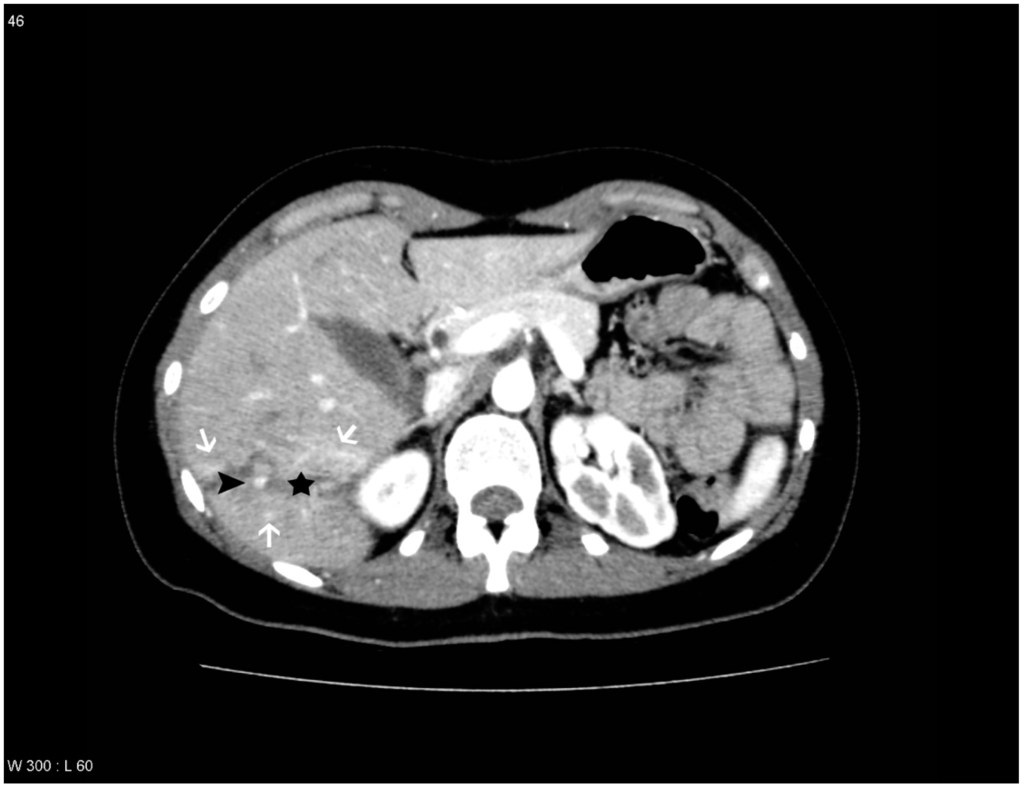

Figure 4. Patient with liver lesion in segment 5, 6, 7 and 8. PS/AF is seen within the lesion and THAD around the lesion. One observer missed the PS/AF. The liver lesion is marked with a black star, the areas with THAD are marked with white arrows and the pseudoaneurysm is marked with a black arrowhead.

The observers diagnosed PS/AF on the follow-up CT scan with an averaged sensitivity of 69.7% and specificity of 96.5% when compared to the gold standard. However, different sensitivities and specificities were found if THAD was included as a variable. If THAD was absent on the follow-up CT scan the averaged sensitivity and specificity were 85.7% and 98.0%, while the averaged sensitivity and specificity decreased to 65.5% and 95.0% if THAD was present (Table 1). This indicates that THAD on the follow-up CT scan can result in both false positive and false negative observations when looking for PS/AF after blunt liver trauma (Figure 3 and Figure 4). Furthermore, it was shown that THAD in this study had a significant influence on the diagnosis of PS/AF for the three residents, as the likelihood of agreement for evaluation of PS/AF between the observers and the gold standard was 89% when THAD was present, and 98% when THAD was absent (p = 0.04).

PS/AF can be recognized and distinguished from THAD by the location, the appearance, and the HU level. PS/AFs seen in 14% of the patients were all oval or round except one, which was linear, and all had focal enhancement with mean HU levels of 170. All PS/AFs were found within the liver lesions (Figure 1 and Figure 4). PS and AF were indistinguishable as stated previously by others [9]. Areas with THAD seen in 54% of the patients had hazy borders, were all found in the periphery of the lesion and with mean HU levels of 100 (Figure 1, Figure 2, Figure 3 and Figure 4).